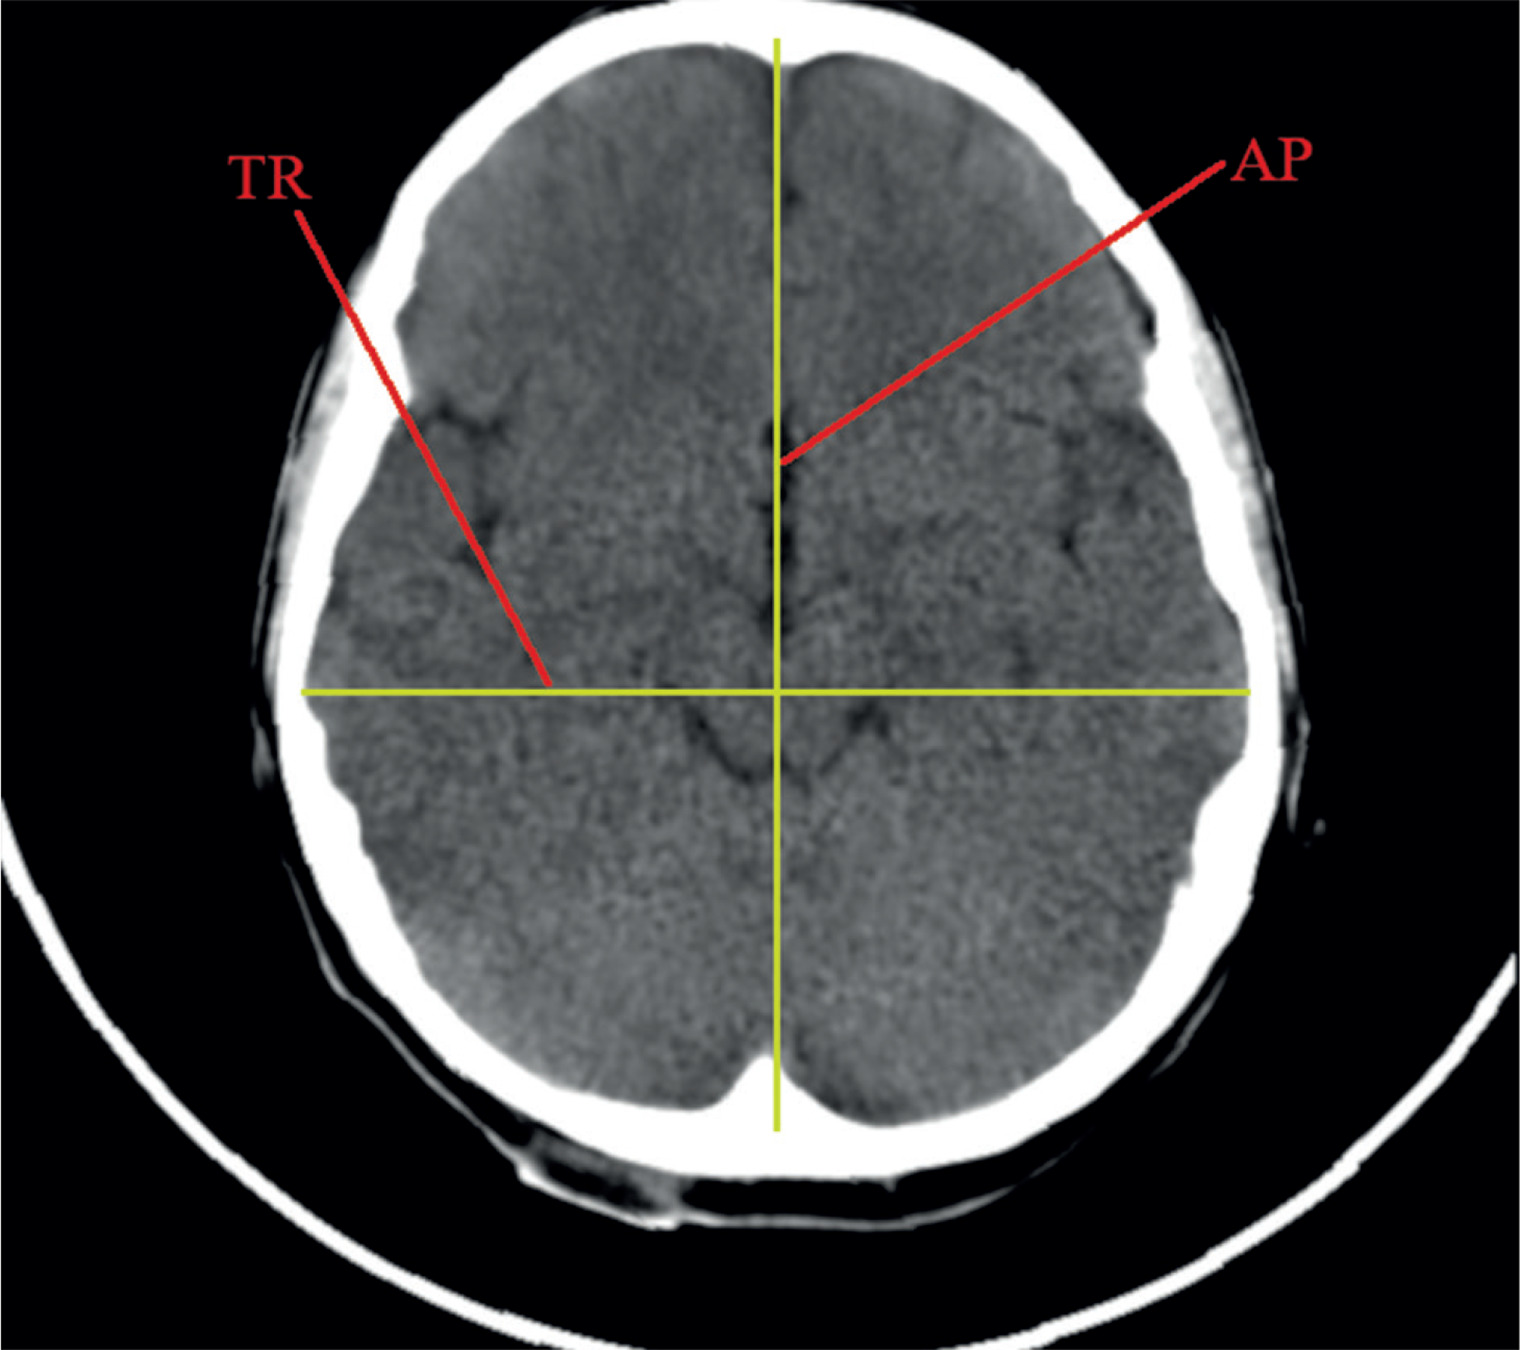

Linear dimensions measured included the following: maximum width of the interhemispheric fissure (IHF) (Figure 1), maximum sagittal dimension of the subarachnoid space at the level of the frontal squama measured on the right (RSS) and on the left (LSS) side, maximum width of the insular cistern measured on the right (RIC) and on the left (LIC) side, maximum sagittal dimension of the Sylvian fissure measured on the right (RSF) and on the left (LSF) side (Figure 1), maximum transverse dimension of the basal cistern (BCTR), maximum sagittal dimension of the basal cistern (BCAP) (Figure 2), maximum sagittal dimension of the prepontine cistern (PC) (Figure 3), maximum transverse internal diameter of the skull (TR), and maximum sagittal internal diameter of the skull (AP) (Figure 4).

All analysed correlations of linear measurements were statistically significant with the child’s age. The increase in the linear dimensions of the fluid spaces with the child’s age was noted for transverse (BCTR) and sagittal (BCAP) dimensions of the basal cistern and the sagittal dimension of the pontine cistern (PC). The above mentioned dimensions showed a positive, weak, but statistically significant correlation with the child’s age (respectively: r(x, y) = 0.23; r(x, y) = 0.29; r(x, y) = 0.30). For the purposes of this study, longitudinal (AP) and transverse (TR) dimensions of the skull were measured, which describe the size of the skull itself. These dimensions were measured based on anatomical points of the skull, hence they showed a direct strong correlation with the age of the child, due to the increase in the skull size (respectively: r(x, y) = 0.62; r(x, y) = 0.57).